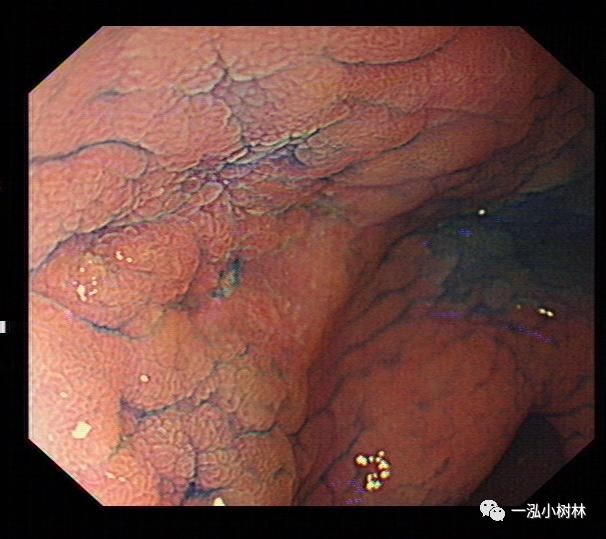

NBI+ME内镜表现:萎缩区域NBI放大可见胃小凹消失或不清晰,树枝状血管显露,黏膜苍白及萎缩边界更明显,多以幽门胃窦部为中心,随着萎缩的加重,胃体黏膜也散见,肠化区域可见胃小凹呈绒毛状,可见到“亮蓝嵴”“白色不透明物质”征。

例3

女性,40岁,萎缩性胃炎+Hp感染